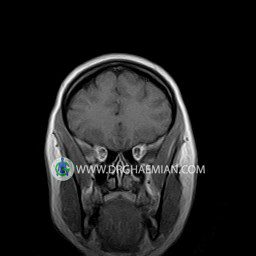

پزشکان اغلب از تصویربرداری ام آر آی برای تشخیص و درمان عارضه های پزشکی که فقط با استفاده از اشعه ایکس یا میدان مغناطیسی و امواج رادیویی قابل مشاهده است، استفاده می کنند. دستگاه ام آر آی تصاویر دقیق از ساختار های داخلی بدن ایجاد می کند. در این کیس نوریت اوربیت چب و سلای خالی بیمار مشاهده می شود.

ORBIT MRI

(with and without contrast)

Technique:Axial T1 , Axial , sagittal , coronal FSE T2 , coronal T1, sagittal fat sat T2 , Axial , sagittal T1 post Gd .

The both orbit are symmetrical and of normal size , with normal development of the orbital cones .

The bony orbital walls show a normal configuration with smooth and, sharp margins .

No foci of bone destruction , no circumscribed expansion of the bony or soft – tissue components of the orbital are evident .

The globes are symmetrical and of normal size and the ocular contents show normal signal characteristics .

The ocular walls are smooth , sharply defined , and of normal thickness .

The retrobulbar fat, ophthalmic vein and lacrimal apparatus are unremarkable .

Evaluable portions of the neurocranium and paranasal sinuses show no abnormalities .

No seen any evidence of ocular herniation

– Small fluid around the left optic nerve with mild edema suggestive for left optic neuritis

– Extension of suprasella cistern to sella with thin pituitary gland in floor of sella ( empty sella )

are seen

REPORTED BY :Dr DrNaser. Ghaemian.